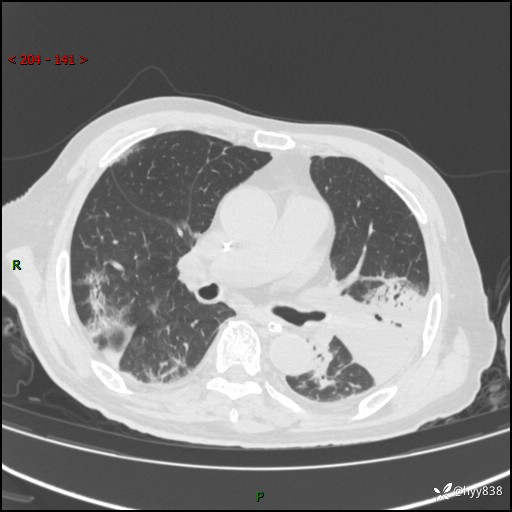

胸部CT平扫(2024.7.24)